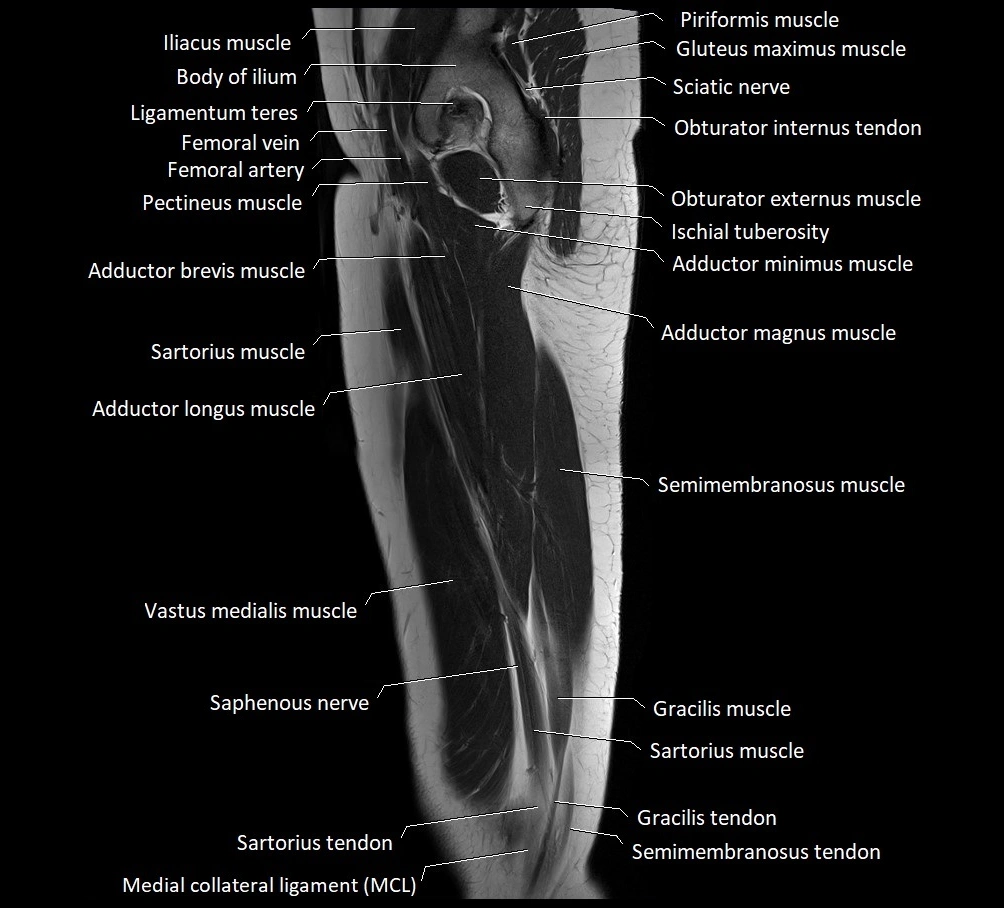

- Iliopsoas muscle

- Body of ilium

- Ligamentum teres (ligament of the head of femur)

- Femoral vein

- Femoral artery

- Pectineus muscle

- Adductor brevis muscle

- Sartorius muscle

- Adductor longus muscle

- Adductor magnus muscle

- Semimembranosus muscle

- Vastus medialis muscle

- Saphenous nerve

- Gracilis muscle

- Sartorius tendon (Distal)

- Gracilis tendon (Distal)

- Medial collateral ligament

- Gluteus maximus muscle

- Superior gemellus muscle

- Obturator internus muscle

- Ischial tuberosity

- Obturator externus muscle

- Quadratus femoris muscle